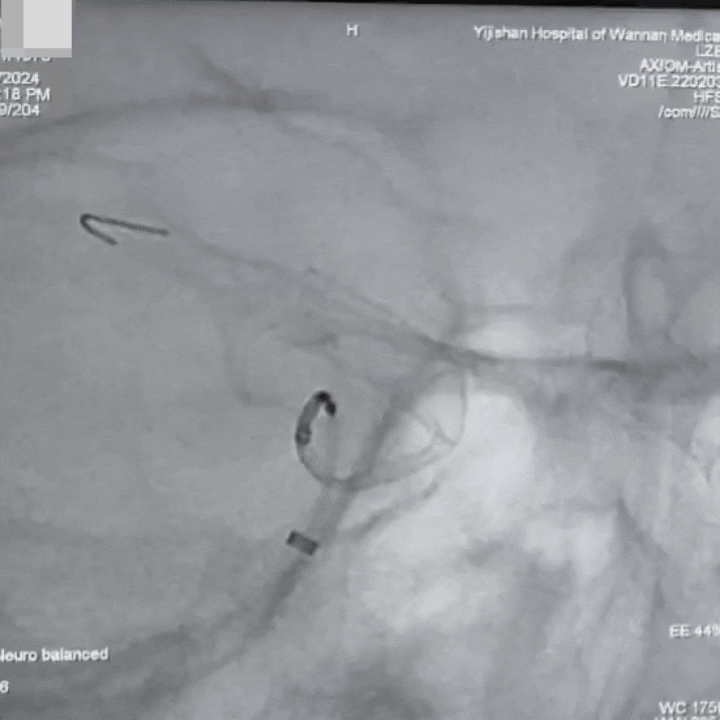

通桥麒麟™血流导向密网支架成功释放。

通桥麒麟™血流导向密网支架完全释放,术后造影。

术后血管造影见动脉瘤仍有显影,瘤腔内造影剂滞留,支架展开,贴壁良好,载瘤血管血流通畅,手术顺利。